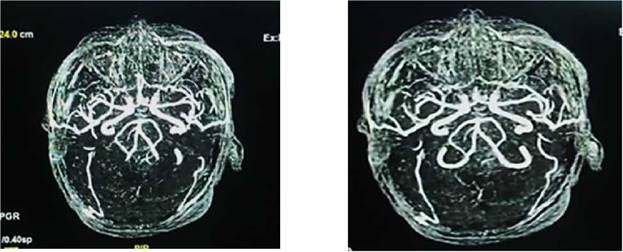

Ingresa con los diagnósticos de: accidente cerebrovascular hemorrágico (peri-troncal); Crisis hipertensiva tipo emergencia; hiponatremia hipotónica hipervolemica; enfermedad renal crónica KDIGO 5 en hemodiálisis; diabetes mellitus tipo 2 mal controlada e hipertensión arterial sistémica. Permaneció bajo monitorización continua de la presión arterial, asociado a vasodilatadores endovenosos (nitroprusiato de sodio 3-5 ug/k/min), seguimiento por el servicio de nefrodialisis, para continuar terapia de reemplazo renal; por otro lado fue evaluado por el servicio de neurocirugía quien indico por el momento tratamiento médico, asociado a medidas de protección cerebral; además fue evaluado por el servicio de cardiología, solicitando una ecocardiograma transtorácico: Hipertrofia concéntrica del ventrículo izquierdo, motilidad regional preservada, fracción de eyección de ventrículo izquierdo (FEVI) 66%; se realizó una Rx de tórax PA que mostro leve redistribución vascular pulmonar, catéter venoso central in situ; por otro lado en fecha 24/05/23 se realiza una angio resonancia magnética de cerebro que muestra hemorragia subaracnoidea y sangre en area prepontina, premedular y peripeduncular, además de cisuras frontoparietooccipitales, dilatación de tercer ventrículo, enfermedad vascular tipo microangiopatia (Figura 2a, b).

Figura 2a, b: angioresonancia de cerebro simple, que muestra hemorragia subaracnoidea y sangre en área prepontina, premedular y peripeduncular, además de cisuras frontoparietooccipitales, dilatación de tercer ventrículo, enfermedad vascular tipo microangiopatia.